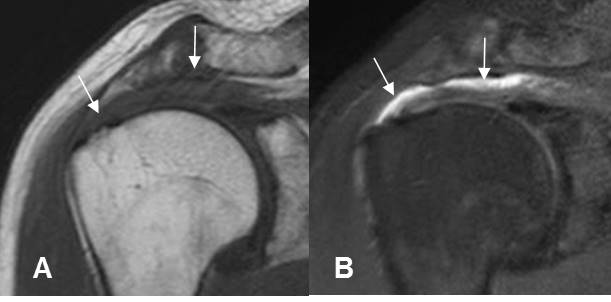

Fig 167. Bursa SASD patológica.

A: RM coronal en T1: Ausencia de la grasa normal en la bursa.

B: RM coronal en STIR. Líquido en la bursa SASD, por proceso inflamatorio.